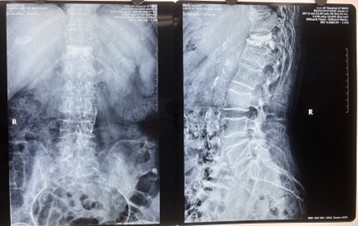

對比一些9英寸的平板C形臂,普愛醫(yī)療PLX119C大平板C形臂,30CM*30CM想(30CM*30CM)的成像范圍,一次性可成像5節(jié)腰椎,有效減少小視野C形臂難以一次性確定傷椎,可能需要進(jìn)行多次拍攝的問題,使得手術(shù)效率更快、更準(zhǔn)確。